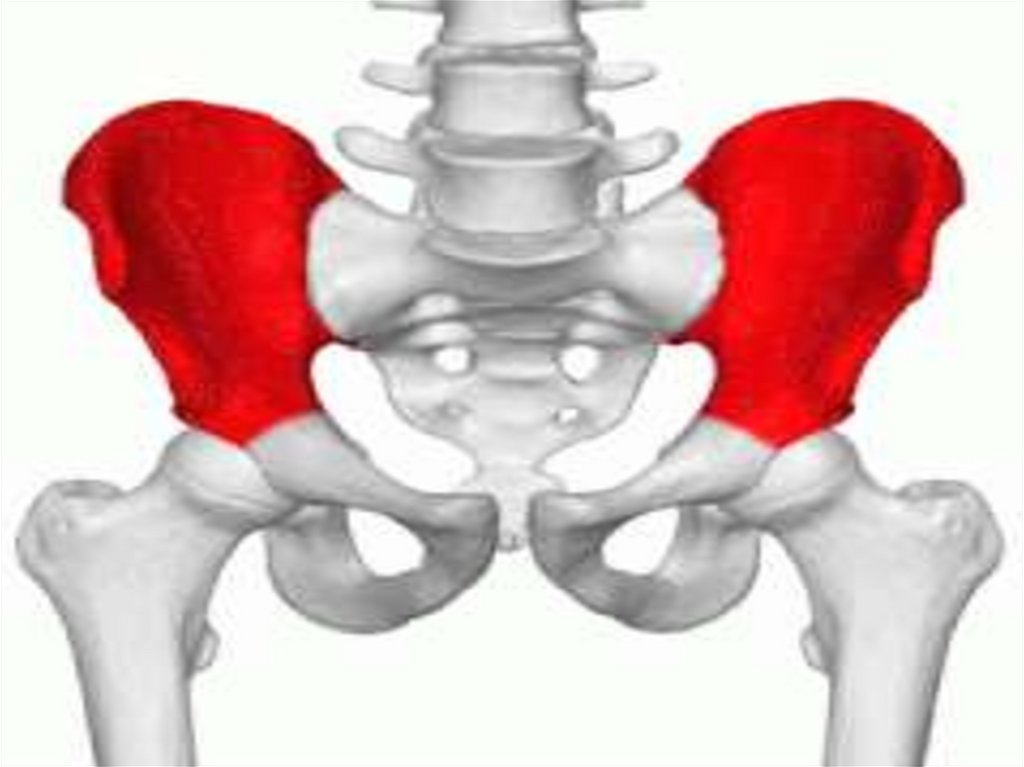

Тазовий пояс (пояс

нижньої кінцівки)

містить кульшові

кістки та крижову

кістку.

4.

Тазовий пояс (пояс нижньої

кінцівки) – cingulum

pelvicum,

містить:

- кульшові кістки – ossa

coxae

- крижову кістку – os sacrum.

5.

Кульшова (тазова) кістка складається os coxae:

- з клубової кістки;

- лобкової кістки;

- сідничної кістки.